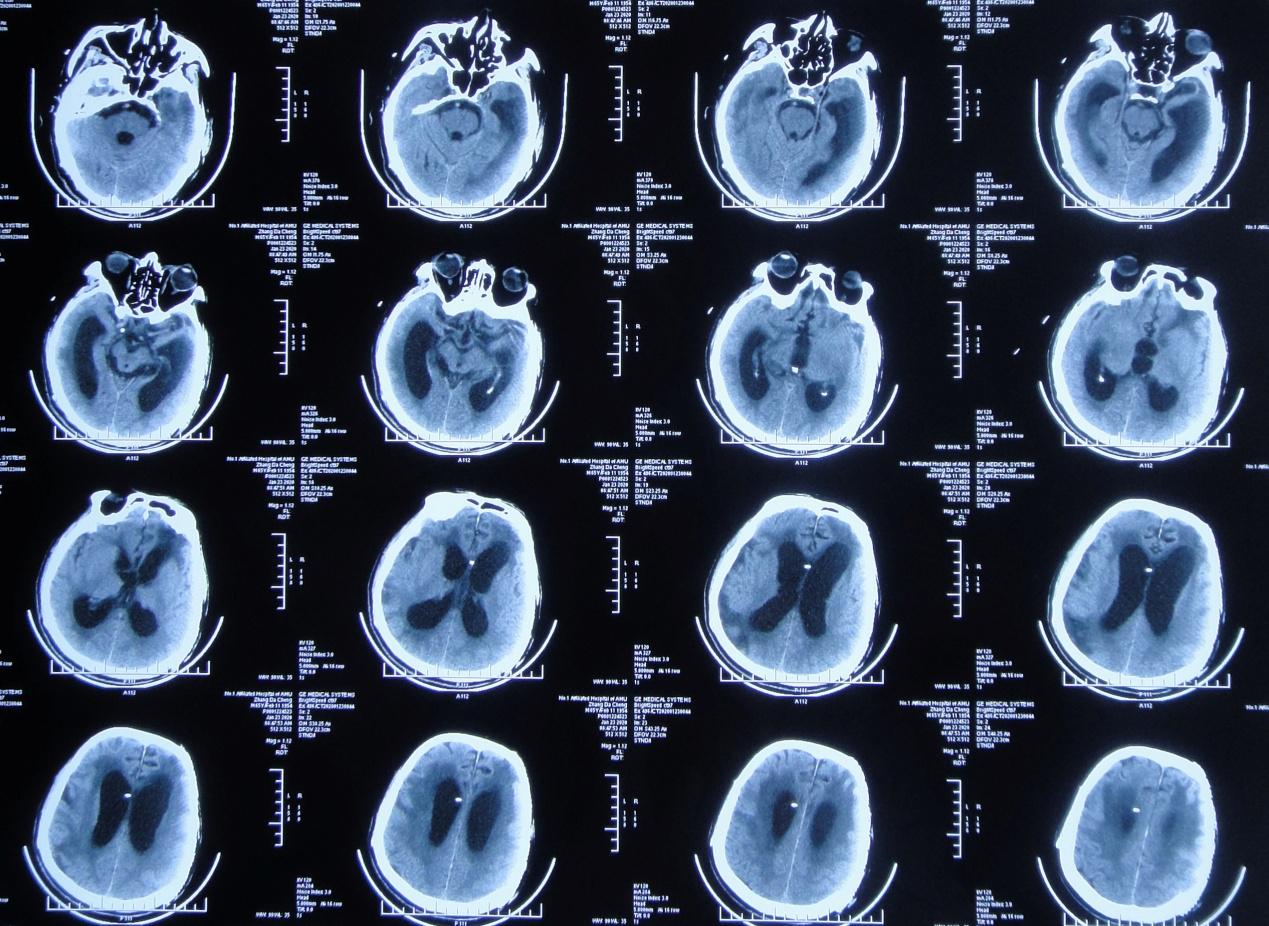

患者2019年7月10日骑电动自行车不慎与大货车相撞,当时意识模糊,可简单对答,四肢可见活动。由120急送至当地安徽省六安市某医院,行头颅CT示大脑多发挫伤(片子丢失),给予甘露醇等脱水治疗,效果差,意识明显加重,呼之不应,呈昏迷状态。当日急转入上级的安徽省某知名省级三甲医院,行头颅CT( 图-1 )示左颞叶脑挫伤伴血肿形成,右额叶脑挫伤,蛛网膜下腔出血,脑疝。

图-1: 2019年7月10日术前头颅CT